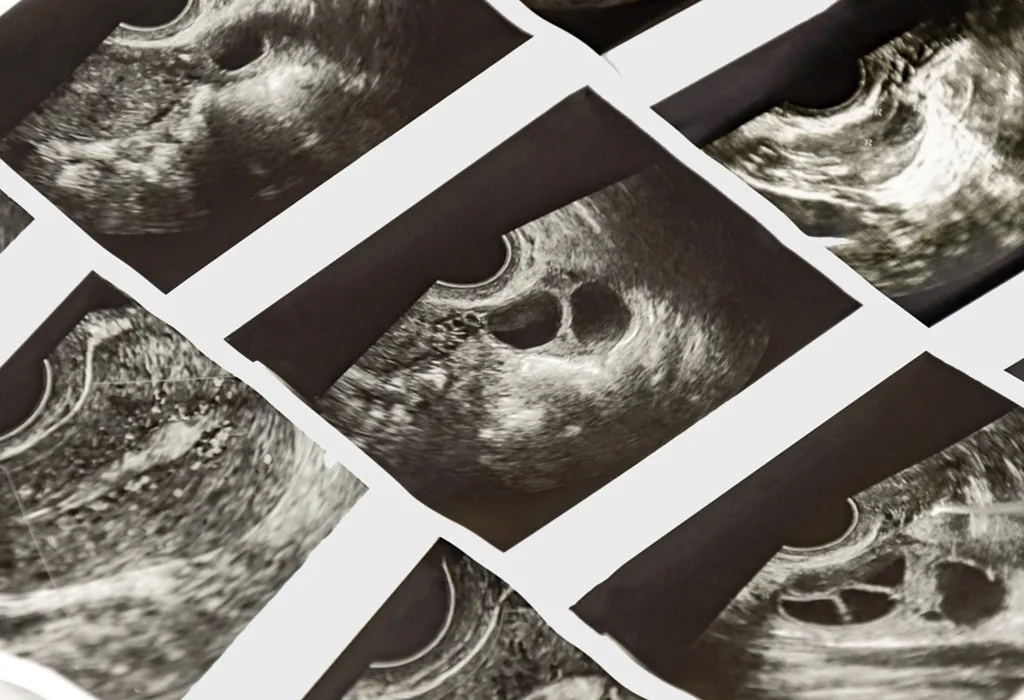

A follicle is an aggregation of cells (similar to tissue) that is found in a woman’s ovaries. Each follicle releases 1 egg in a lifetime. Women are born with roughly 400,000 follicles. A follicular study and pregnancy are closely related; a follicular study is carried out in order to understand whether the person is ovulating at the time. Follicular tracking involves the study of the development of the follicle, in order to find out how close to ovulation a woman is. It involves a simple series of vaginal scans which help identify the stage of the menstrual cycle the woman is in currently.

The method by which the follicular monitoring procedure is done is called ultrasound scanning. The ovarian follicles are examined, and pictures of the internal organs are taken by inserting small plastic probes into the vagina. The process is carried out by certified sonographers. The probes themselves will be extremely hygienic and clean. You will need to lie down in the stirrup position so that the scan can be done. With a sheet covering you from the waist down, the probes are inserted. These probes emit sound waves in the ultrasound frequencies, using which the images are captured. The sonographer will be able to accurately predict the time the egg will be released, based on how the walls of the uterus have thickened. Therefore, you can plan your efforts to conceive in order to maximise your chances. The follicular study process is, therefore, of great use if you trying to have a child.

It is common to carry out four to six scans during a cycle, in order to better ascertain when ovulation will take place. The initial scan is called the baseline scan, and it helps the doctor understand the initial stage of the follicle with great certainty. From there on, the doctor schedules the scans at the best times to follow the development of the uterine follicles. The inner lining of the uterus and the growth of the follicle are checked during each scan, and finally, the doctor gets a clear idea of when the woman will be ovulating. These scans might be carried out within an eleven-day window during the cycle of the woman.